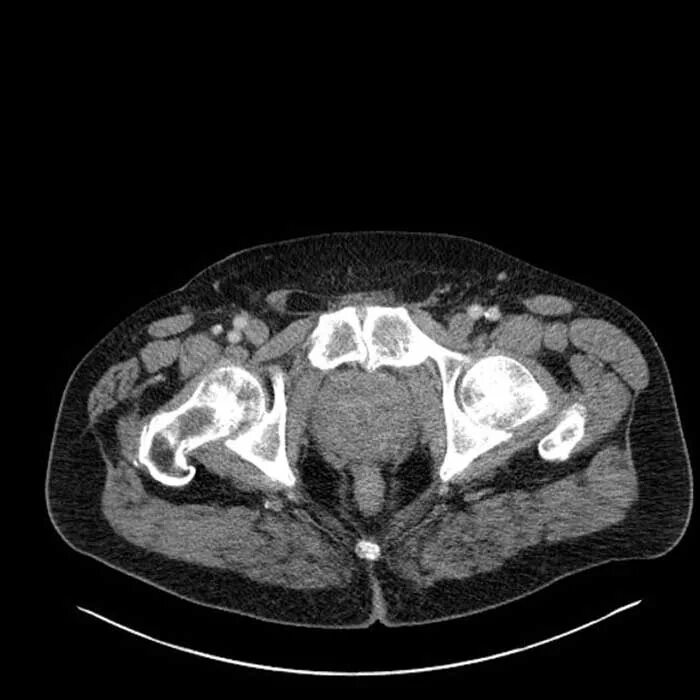

Бактериальная простата